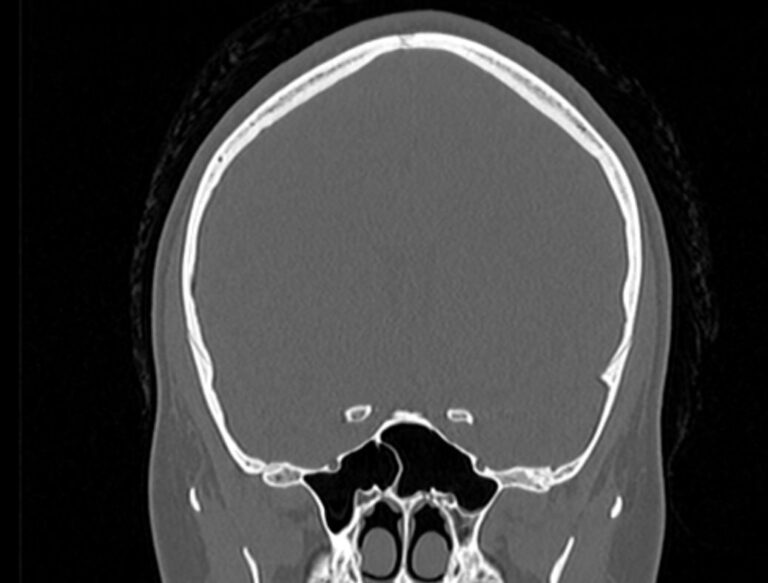

Мультиспиральная компьютерная томография является наилучшим методом диагностики патологии костей черепа. В основе методики лежит использование рентгеновского излучения с последующей цифровой обработкой полученных данных и получения трехмерных реконструкций изображений.

Костная ткань отличается высокой плотностью и способна в большой степени поглощать рентгеновские лучи. Поэтому на послойных снимках, полученных при проведении мультиспиральной КТ черепа можно детально рассмотреть свод черепа, кости лица, основание черепа. Это позволяет с наибольшей точностью визуализировать различные объемные образования, такие как остеомы, дифференцировать фиброзную дисплазию или костные метастазы. Преимуществами методики КТ является отличная визуализация костных структур, быстрота выполнения процедуры и доступная цена. Все это делает КТ незаменимой при диагностике травматических повреждений (например переломов основания черепа или орбит), аномалий развития, при планировании оперативных вмешательств.